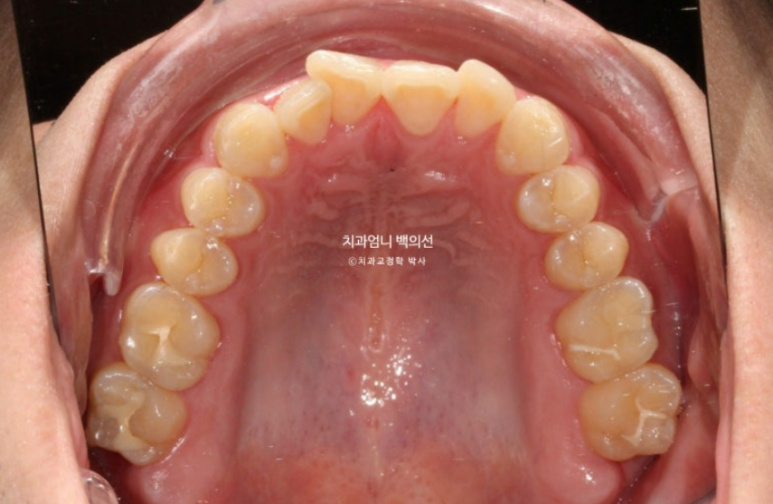

어금니 배열도 좋은 편이라 앞니 부분교정 권유드렸습니다.

앞니 부분교정에서는 어금니를 움직이지 않으므로 삐뚠 치아들을 배열하기 위해 필요한 공간을 앞니쪽에서 얻어야 합니다.

MTA 부분교정을 제1소구치부터 제1소구치까지 위 아래 8개씩 부착하여 치료를 시작했습니다.

아래 앞니 중 안으로 쏙 들어가 있던 치아는 교정치료 전 후 위생 상태의 확연한 차이가 납니다.

치아가 삐뚠 부분에는 치태와 치석이 쉽게 쌓이는 데다가 일반 양치질로는 접근이 어려워 깨끗하게 닦이기 쉽지 않습니다.

교정 후 배열이 가지런해지니 유독 청소가 안되던 부위가 평소하는 양치질 만으로도 말끔해졌습니다.